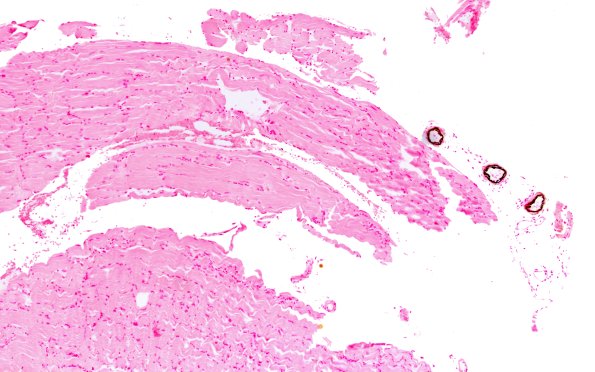

1B1 Calciphylaxis (Case 1) Von Kossa 10X 1

1B1,2 Von Kossa stained sections showing the stippled depositions of darkly stained calcium within the vessel walls.